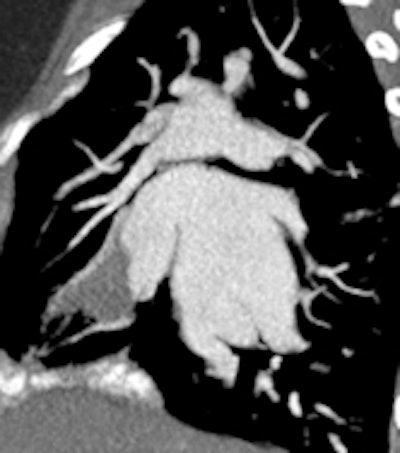

A 14-year-old patient with transposition of greater arteries and gross pulmonary arterial hypertension. CT angiography study shows aneurysmal dilation of the pulmonary arteries (top left, top right), with thrombus in the right middle lobe pulmonary artery (bottom left). There is partial anomalous pulmonary venous return from the right upper lobe to the superior vena cava (arrow, bottom right).